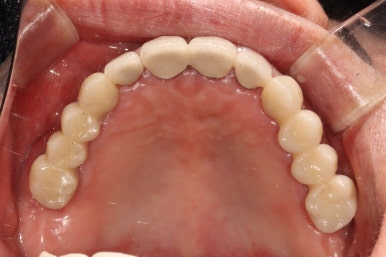

그렇게 완성된 최종 보철물 형태입니다.

임시치아와 다르게 지르코니아 크라운으로 제작되어 훨씬 단단하고 매끈하고 이상적인 형태를 가진걸 보실 수 있으실거에요.

위 아래 앞니 모두 적절한 길이로 회복이 되었고, 어금니도 이상적인 형태를 보여주고 있습니다.

식사 시 음식이 덜 끼도록 치아와 치아사이를 최대한 닫아놓은 모양입니다.

위아래 모두 아주 이상적인 형태로 제작된 치아모양의 지르코니아 크라운을 보실 수 있을거에요.

이 정도면 전체 구강 재건 (full arch rehabilitation)이라고 불러야 합니다.